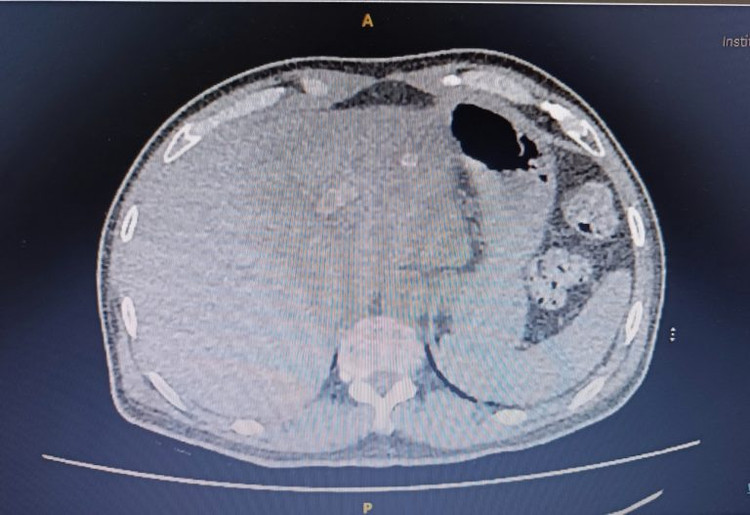

| Hình ảnh CT ổ bụng thấy khối thoát vị thành bụng - Ảnh BVCC |

Qua thăm khám lâm sàng và chụp CT ổ bụng, các bác sĩ khoa Ngoại Tổng quát BVĐK Xuyên Á đã phát hiện một khối thoát vị thành bụng ở vị trí vết mổ cũ vùng rốn. Để xử trí khối thoát vị cho người bệnh, các bác sĩ đã hội chẩn và quyết định phẫu thuật nội soi đặt lưới trong phúc mạc điều trị thoát vị thành bụng (IPOM).